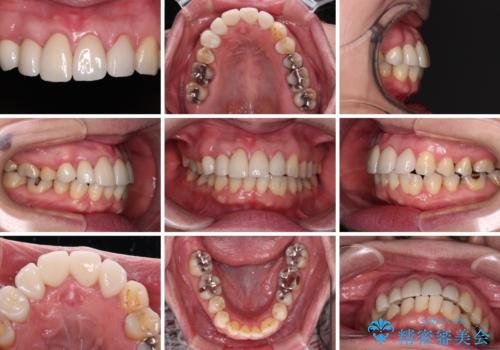

また、当初は予定しておりませんでしたが、歯列が整ったことで前歯の歯の色や形が気になり、矯正治療後にオールセラミッククラウンにて補綴治療することとしました。

あっという間に気になっていた歯列が改善され、自然な口元になり、患者様には大変満足していただきました。